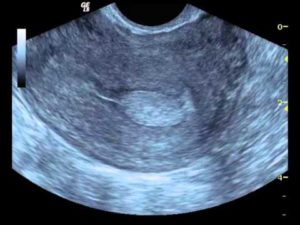

Квалифицированный врач без труда отличит, полип или беременность он видит на мониторе приспособления. Плодное яйцо темного цвета и округлой формы, тогда как нарост светлый, имеющий цилиндрическую форму.

Отличить полипозное новообразование в матке от плодного яйца не составит труда – они отличаются как по форме, так и по цвету. Плодное яйцо более округлое и имеет темную окраску, а полип – более светлый.

Плодное яйцо — анэхогенное образование, то есть темное пятно круглой или овальной формы с четким контуром. Это потому что внутри содержится жидкость, в ней выделяется светлый эмбрион. Увидеть плод можно уже на 2 неделе.